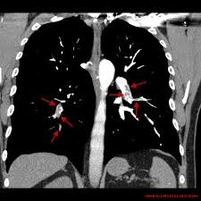

Zator tętnicy płucnej jest główną przyczyną chorobowości I śmiertelności wśród chorych poddawanych zabiegom kardiochirurgicznym w trybie pilnym, z całkowitą śmiertelnością wahającą się od 6% do aż 85%. Choć leczeniem pierwszego rzutu jest postępowanie niechirurgiczne lub interwencja przezskórna, to u chorych we wstrząsie kardiogennym leczenie operacyjne ciągle pozostaje metodą z wyboru. Nasz ośrodek regularnie wykonuje operacje embolektomii tętnicy płucnej, których rezultat jest lepszy, niż podają aktualne doniesienia. W związku z tym przeprowadziliśmy retrospektywną analizę wyników leczenia chorych z zatorem tętnicy płucnej i rodzaju anestetyków stosowanych podczas leczenia.

Retrospektywny przegląd wyników leczenia 40 chorych poddawanych operacji pilnej embolektomii tętnicy płucnej w ciągu 4 lat (2008-2012) w naszym ośrodku. Badanie zostało przeprowadzone w szpitalu uniwersyteckim trzeciego stopnia referencyjności. Dokonano przeglądu historii chorób pacjentów hospitalizowanych z powodu zatoru tętnicy płucnej. W związku z badaniem nie były przeprowadzone żadne interwencje. Dokonano przeglądu dokumentacji anestezjologicznej, wyników badań echokardiograficznych oraz opisów zabiegów, po to by ocenić w analizowanej grupie chorych: funkcję układu krążenia, potrzebę wykonania pilnego chirurgicznego zespolenia systemowo-płucnego i stopień chorobowości.

Dokonano przeglądu dokumentacji medycznej 40 chorych. Niestabilność hemodynamiczna występowała w 12,5% przypadków w czasie indukcji znieczulenia i wymagała wytworzenia pilnego zespolenia systemowo-płucnego. Kolejne 17% chorych, którzy byli stabilni podczas indukcji, rozwinęło wtórną niestabilność hemodynamiczną wymagającą pilnego zespolenia systemowo-płucnego podczas otwarcia osierdzia bądź manipulacji w jego zakresie. Jeden chory zmarł podczas hospitalizacji. Chorzy, którzy wymagali wytworzenia pilnego zespolenia systemowo-płucnego podczas indukcji znieczulenia ogólnego, zwykle otrzymywali większą dawkę anestetyków niż chorzy z pozostałych grup. Wśród chorych wymagających pilnego zespolenia systemowo-płucnego podczas manewrów w obrębie osierdzia, u których indukcja znieczulenia przebiegła gładko, nie zidentyfikowano czynników ryzyka niestabilności hemodynamicznej.